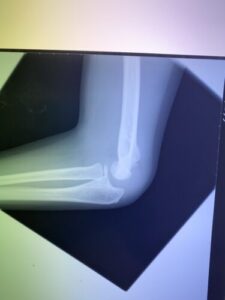

春日部市市民活動センター(肘関節脱臼)

肘関節前方脱臼の1症例について